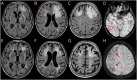

Figure 1. Spontaneous ARIA-like Imaging Findings at Presentation and After Radiologic Remission at 3-Month Follow-up of a Patient With Probable CAA-ri

(A and B) Fluid-attenuated inversion recovery (FLAIR) images (axial sequences) at presentation show cortico-subcortical regions of hyperintensity suggestive of vasogenic edema and sulcal effacement on both hemispheres (red arrows). (C) Susceptibility-weighted images show microbleeds (red circles). (D and E) MRI 3 months after corticosteroid pulse therapy (5 IV boluses of 1 g/d methylprednisolone followed by 1 mg/kg oral prednisone daily and slow tapering off over several months) showing the disappearance of the acute inflammatory white matter hyperintensity lesions in the corresponding planes of FLAIR sequences indexed at presentation. ARIA = amyloid-related imaging abnormalities; CAA-ri = cerebral amyloid angiopathy–related inflammation.